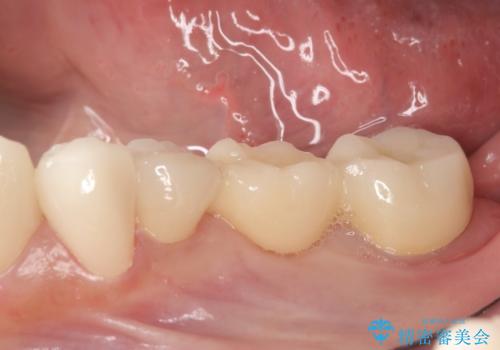

- 左下の銀歯を前の歯に合わせて白くしたいといらっしゃった方の症例です。

前歯部のシェードに合わせ、左下4及び左下567ブリッジをオールセラミッククラウンにて補綴しました。

今回用いたオールセラミッククラウンはジルコニアフレームという白い素材の上にセラミックを盛っているため、審美性が非常に高いのが特徴です。

また、ジルコニアは人工ダイヤモンドの材料にも使われているほど高い強度を持っており、そのためオールセラミッククラウンは審美性だけでなく、奥歯やブリッジの補綴も可能とするクラウンです。